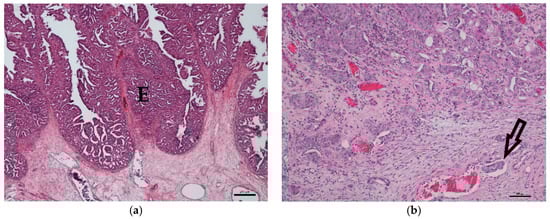

3.1. Histology

3.2. COX-2 Immunohistochemistry